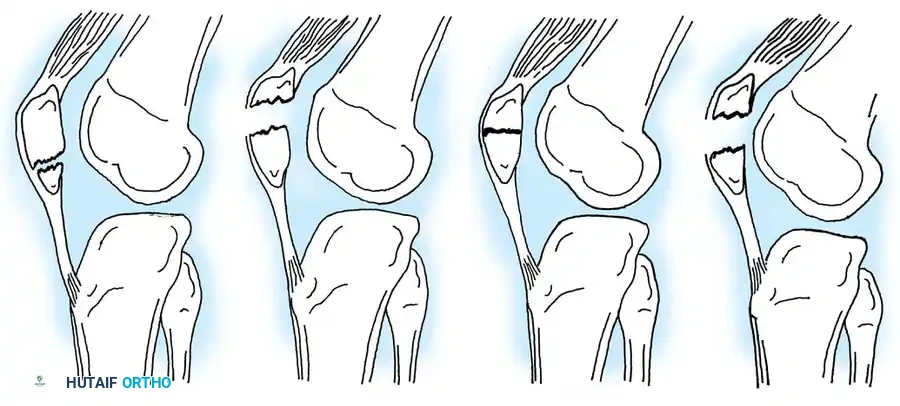

The management of tibial eminence fractures is dictated by the Meyers and McKeever classification system, which assesses the degree of displacement and the presence of a cartilaginous hinge.

- Type I: Non-displaced or minimally displaced fracture. The bony fragment rests in its anatomical bed.

- Type II: The anterior portion of the eminence is elevated and displaced proximally, but an intact cartilaginous hinge remains posteriorly. The fragment resembles a bird's beak.

- Type III: Complete displacement of the fragment with no cortical or cartilaginous continuity. The fragment may be rotated.

- Type IV (Zaricznyj modification): Comminuted fracture of the eminence.